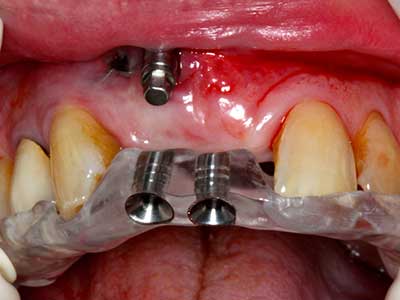

Wie sich in der Vergangenheit gezeigt hat stellt prinzipiell jeder knochenchirurgische Eingriff eine mögliche Indikation für die Piezochirurgie dar. So lässt sich die Präparation des mobilen Segmentes bei der Distraktionsosteogenese (Abb. 23-25) und der Sandwichosteotomie mit speziellen Ansätzen bewerkstelligen, ohne die für den Erfolg beider Techniken essenzielle Blutversorgung des krestalen Anteils zu gefährden (Gonzalez-Garcia, Diniz-Freitas et al. 2008).

Abb. 21: Ausgedehnter OK-Frontzahndefekt mit Indikation zur Distraktionsosteogenese bei vernarbtem Weichgewebe nach Vor-Operation.

Abb. 22: Das mobile Segment kann präzise mit der dünnen Osteotomiesäge (W&H Piezomed) separiert werden.

Abb. 23: Finale Mobilisation des palatinal gestielten Distraktionssegmentes mit dem Meissel.

Abb. 24: Anbringen des Distraktors (TRACK-System, KLS Martin).